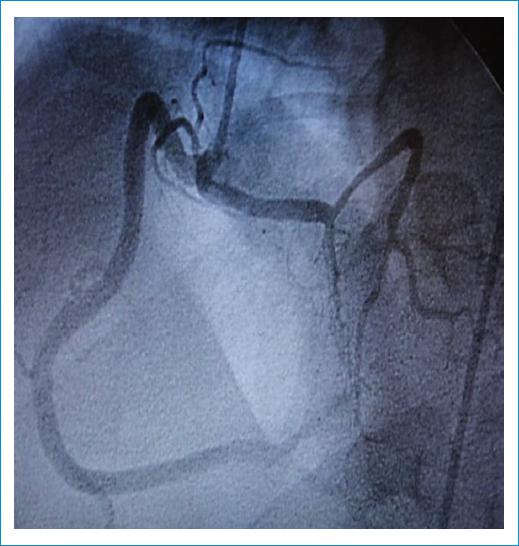

Figura 1 Cinecoronariografia dónde se observa el origen anómalo de la arteria descendente anterior desde el seno derecho.

Se presenta el caso de un varón de 58 años con estenosis aórtica grave y válvula bicúspide, remitido para sustitución valvular. Como parte de su evaluación prequirúrgica se realizó una cinecoronariografía que reveló un origen anómalo de la arteria descendente anterior, la cual nace desde el seno coronario derecho, junto a la coronaria homónima (Fig. 1). Ante este hallazgo se solicitó una angiotomografía coronaria para definir el trayecto del vaso, precisándose el origen común de las arterias descendente anterior y coronaria derecha. La primera tenía un curso entre la raíz aórtica y la arteria pulmonar, y su recorrido subpulmonar, ingresando posteriormente en el tabique interventricular (tercio superior) a través de un curso transeptal. Así mismo, se observó el origen de la arteria circunfleja desde el mismo seno coronario, pero con un ostium independiente y un trayecto retroaórtico (Figs. 2-3). El origen anómalo de la arteria coronaria izquierda en el seno de Valsalva derecho tiene una prevalencia del 0,02-0,03%, resulta infrecuente su asociación con válvula aórtica bicúspide y existen pocos casos reportados. Como particularidad agregada, todas las arterias coronarias se originan en el mismo seno de Valsalva. Al paciente se le practicó reemplazo valvular con prótesis mecánica y baipás mamario a la descendente anterior. La evolución posoperatoria resultó libre de eventos.